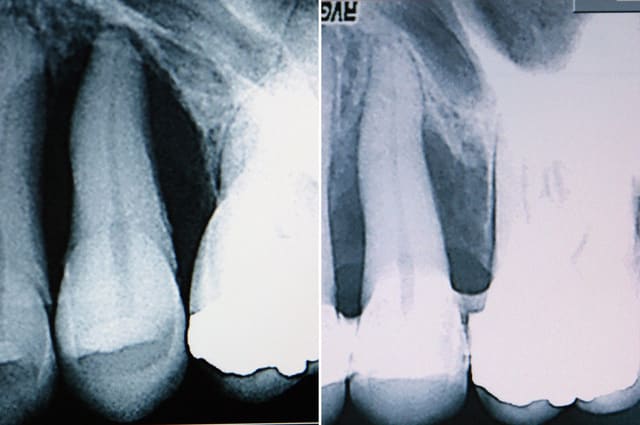

attelle en fibres puis surf puis inj de parocline... j' y croyais pas....et pourtant...

emdogain pour la prochaine étape....

j’ai regardé la radio 76578990 fois… bin waow…

moi j'attendrais peut être encore un peu avant emdogain .. tu peux encore en obtenir par cicatrisation naturelle .. ca fait 2 ans que je dis que le parodonte peut être déminéralisé mais qu'il peut rester un ancrage organique !

combien de temps entre le debut et la seconde radio .. la cicatrisation d'un cas comme ca en naturel c'est 8 mois mini

attention à l'endodonte qui pourrait être le point faible ensuite

cicatrisation à 6 mois

par contre je suis persuadé qu'il ne faut pas sonder pas irriguer plus qu'il ne faut surtout si comme dans le cas ou celui de Carole la composante occlusale prend le dessus sur la composante infectieuse .. Si abcès en urgence atb probabiliste de type metronidazole ...pas de tests . J'ai mis volontairement la sonde sur la photo pour montrer qu'à 6 mois seulement j'avais sondé pas avant.au niveau muqueux c'est cicatrisé mais au niveau osseux il faut encore 3 mois au moins